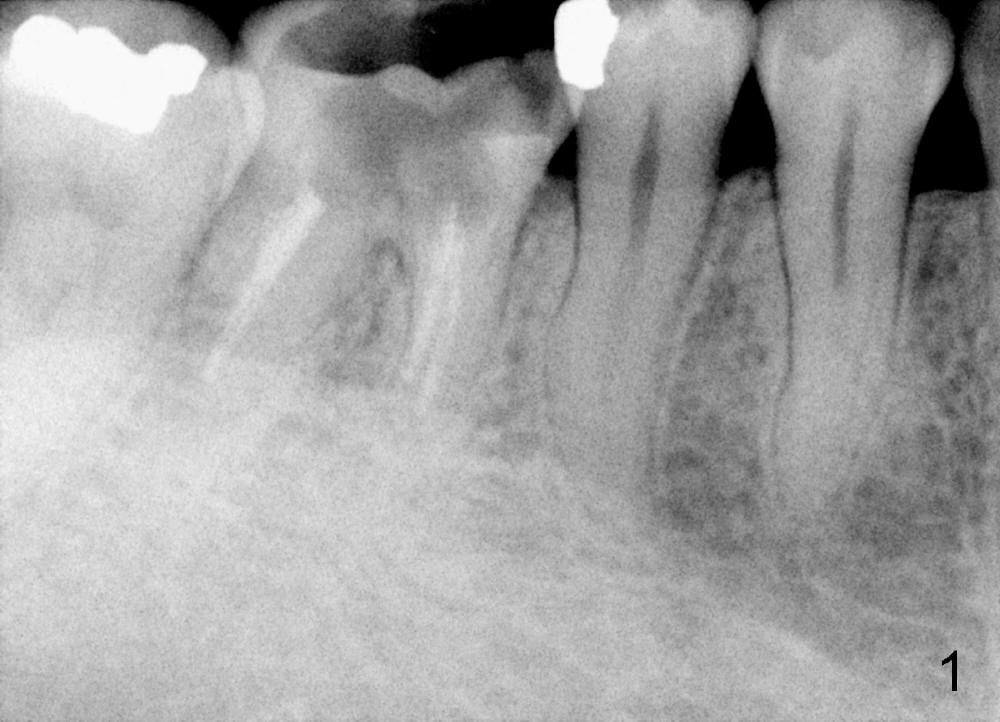

A 38-year-old lady agrees to have implant placement 7 years after loss of the crown of the lower right first molar (Fig.1,2). When the tooth is extracted, the septum is found to be low (Fig.3,4). To confirm it, a PA is taken (Fig.5). To initiate an osteotomy in the septum, it is trans-sectioned with thin osteotomes as shown in Fig.4 insert (black line). A 2 mm pilot drill is placed in the septum (Fig.6: P). The osteotomy is enlarged by 2.5-4.0 mm reamers (Fig.7,8), followed by insertion of 6x17 mm tapered tap at the depth 14 mm (Fig.9). The osteotomy is further enlarged by 4.5 and 5.0 mm reamers. A 6.0x14 mm one piece implant is placed initially. The trajectory is not ideal. A 6.0x14 mm one piece implant is placed initially. The trajectory is not ideal. The implant is removed from the osteotomy partially and reinserted with improved trajectory (Fig.11, compare to Fig.10 (red line)). Primary stability is high. There is not much bone mesiodistally so that the trajectory is easily changed in that direction. After abutment preparation, mixture of autogenous bone (harvested from reamers) and allograft is placed in the residual mesial and distal sockets (Fig.12). To contain the bone graft, an immediate provisional is placed (Fig.13 P). The occlusal plane of the provisional is significantly lower than that of the adjacent teeth to avoid micromovement of the implant. The patient is advised to eat soft food on the left side. Six days postop, the patient returns for prophy. The provisional is removed; the bone graft appears to be incorporating into the socket (Fig.14). After recementation, the provisional remains in place for 3.5 months; PA shows increased bone density in the mesial and distal sockets (Fig.15, compare to Fig.5,11). Due to insurance coverage, the patient defers fabrication of definitive restoration for at least 7 months. The immediate provisional is finally lost 8.5 months postop: the gingiva attaches to the 1-piece implant (Fig.16), while the density of the mesial socket increases (Fig.17 *) with formation of the cortex (lamina dura) coronally (v). Before the provisional (Fig.18 P) is removed for cementation of the definitive restoration, black shadow (*) is noted over the buccal gingiva. It is partially due to buccal placement (Fig.19) and partially due to buccal atrophy over a period of 10.5 months postop. How to prevent buccal placement? Positioning the first pilot drill in the septum buccolingually is a key. Eleven months post crown (Fig.20 C) cementation, the black shadow remains, but there is no tenderness. If the implant threads are immediately underneath the periosteum, there is tenderness.